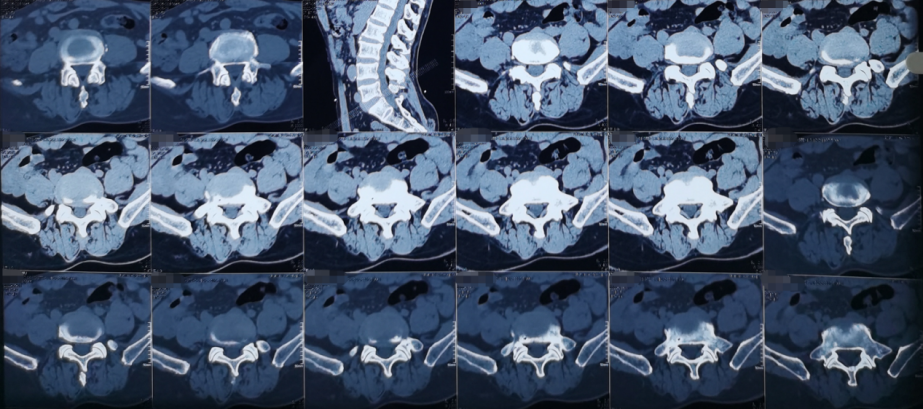

熊东主任接诊后,建议患者进行腰椎CT、核磁共振等影像检查和各项查体,结合各项检查结果,最终确诊患者为“腰椎间盘突出症(腰5/骶1,中央型)”。除此之外,患者还有相应水平的硬膜囊受压与腰椎骨质增生。

术前影像学资料:

“之前一直说是腰椎间盘突出症,我搞不明白,腰椎的问题,怎么让两条腿又疼又麻?”刘大爷在门诊时将自己的不解问了出来。熊东主任为他这样解释,“您的这种情况其实是正常的,腰椎间盘突出症不一定都会引起腰痛等症状。但是由于腰椎间盘突出会压迫到腰神经,腰神经掌管着下肢的运动和感觉,所以就会出现下肢的放射性疼痛、麻木、无力。一般来说,腰椎间盘突出症患者多出现一侧神经受压,常常表现为一侧下肢症状,但是您的片子上显示是中央型,两边的神经都有受压,所以双腿都出现了症状。”